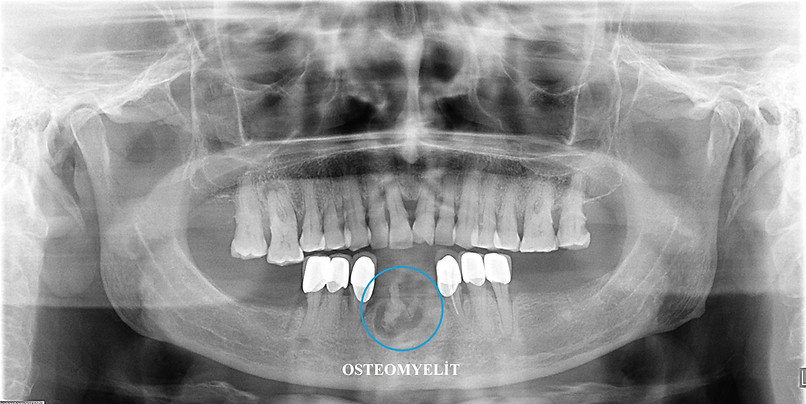

osteomyelit